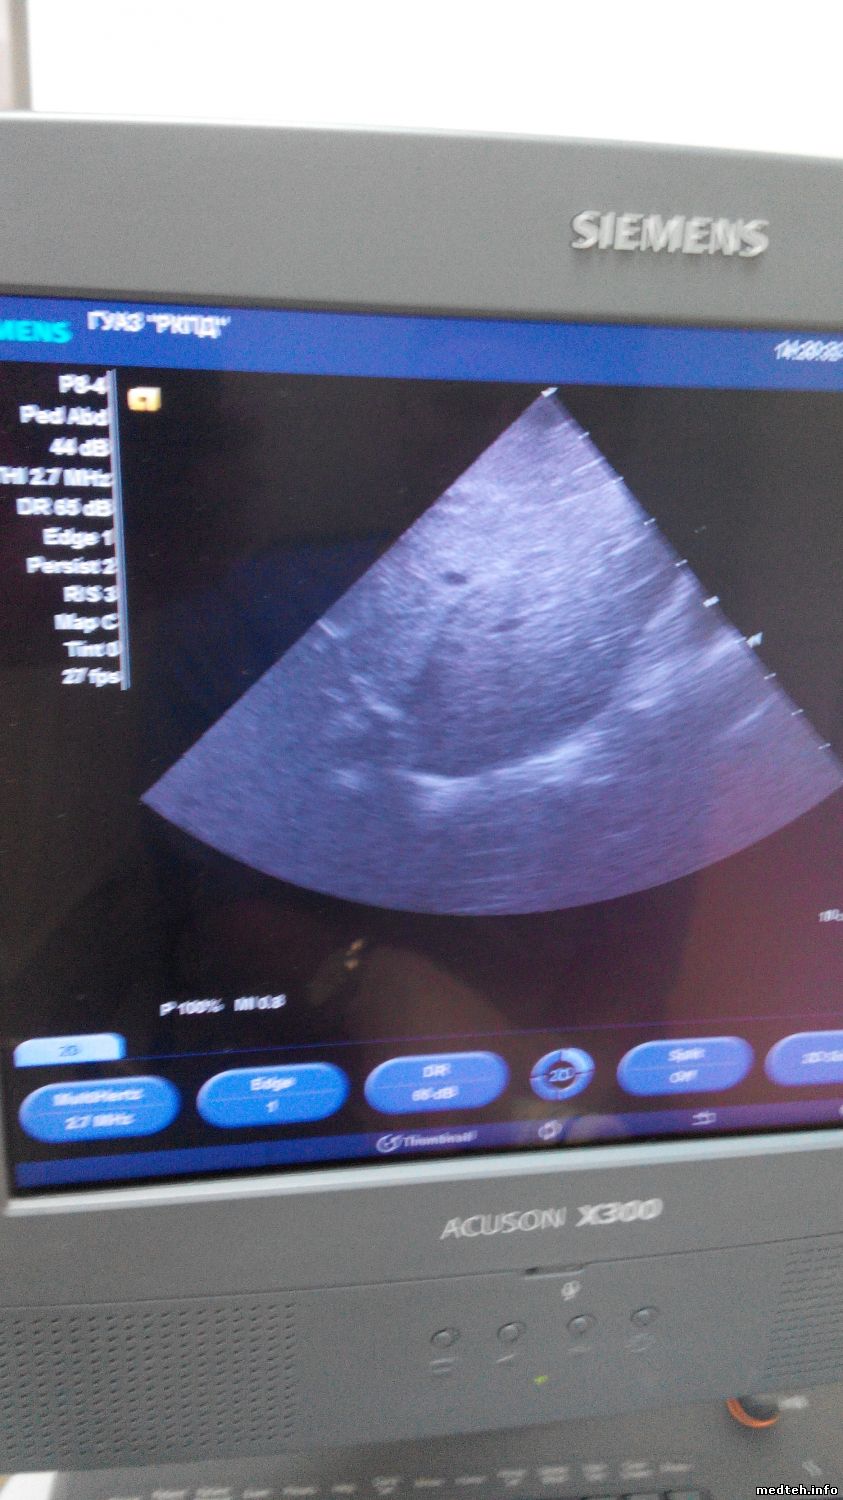

По поводу изображений с датчика. Для фазированного картинка вполне нормальная. А что с линейкой и конвексом?

Итог: С подменными от моего не исправного УЗИ результата не дало, мои 2 секторных датчика Р4-2 и Р8-4 на том аппарате работают хорошо!!!!!!!!!! unknown

А вот как ведут эти же датчики на исправном УЗИ аппарате:

Без помех- строго по делу!!!